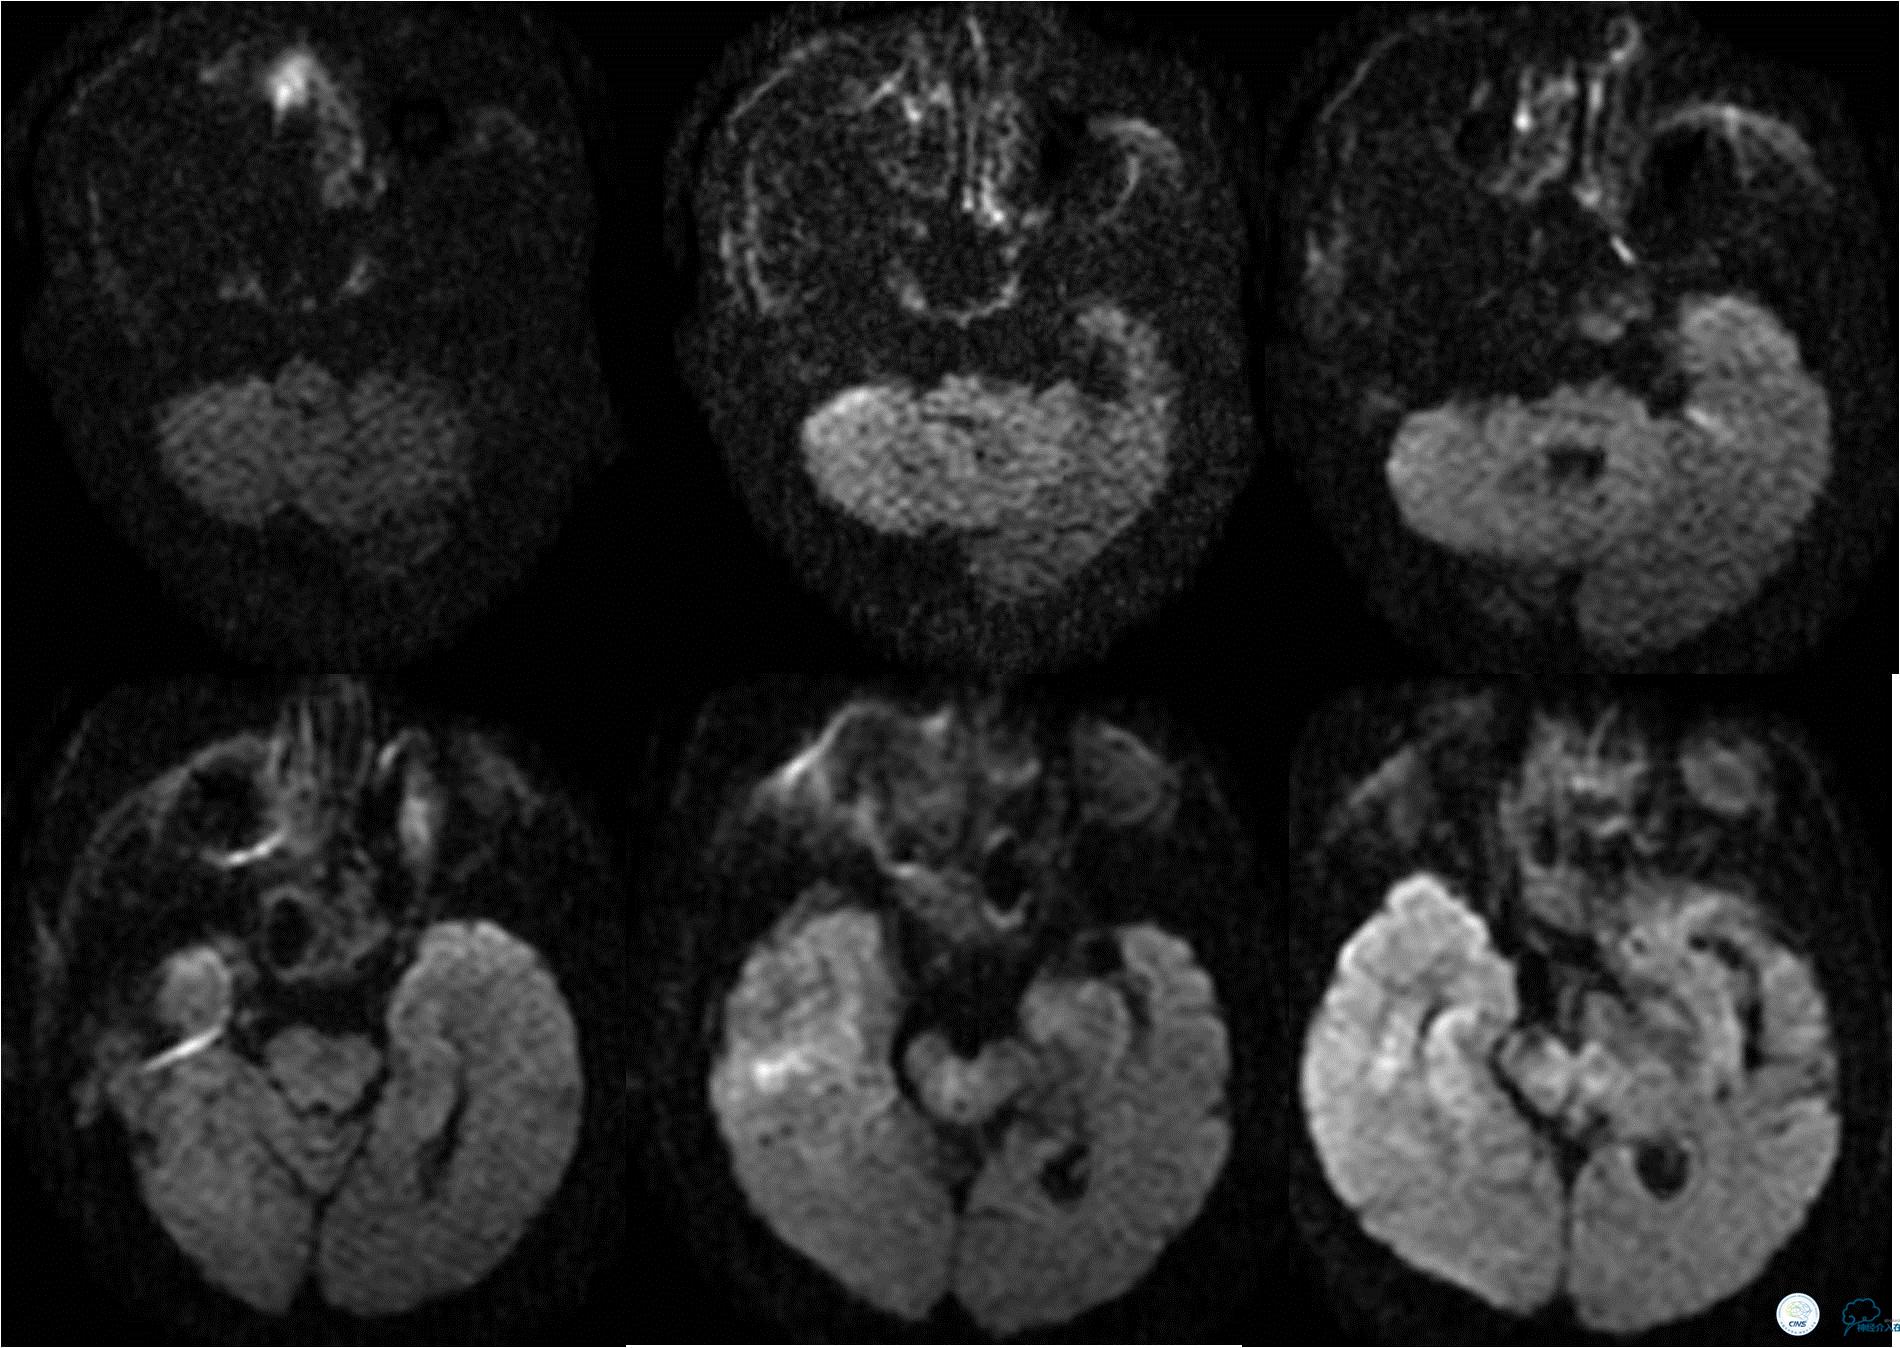

》术后10天,复查MRI